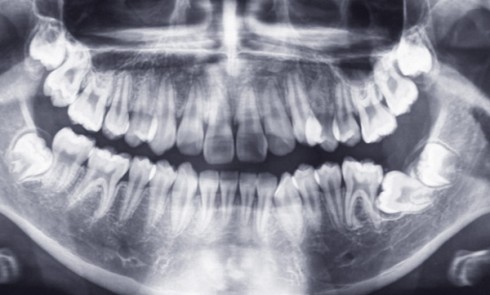

Article réservé à nos abonnés Cas d’inclusions multiples atypiques

Présentation du cas clinique Marine consulte, avec une radiographie panoramique (fig. 1), au service d’Odontologie du CHU de Bordeaux. Elle est...